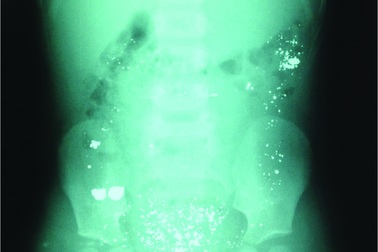

Nhiễm độc thạch tín từ nguyên nhân không ngờNgười đàn ông nhập viện với chẩn đoán ung thư tế bào gai, vảy nến, theo dõi nhiễm độc asen mạn tính. Nguyên nhân có thể do sử dụng nước giếng khoan và uống thuốc không rõ nguồn gốc trong nhiều năm.